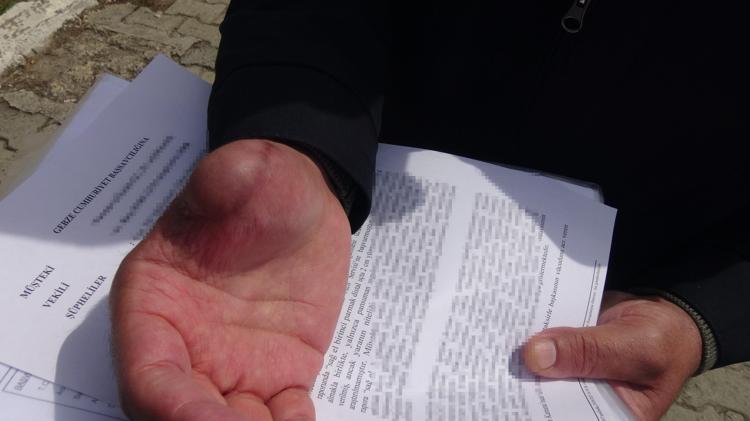

Nurettin Güleryüz, ampütasyon sonrası sağ kolunda ağrı ve şişlik şikayetleri yaşayınca Darıca Farabi Eğitim ve Araştırma Hastanesi’ne başvurdu. Burada yapılan tetkiklerde, Güleryüz’ün kolunda 14 milimetre boyutunda yabancı cisim bulundu. Marmara Üniversitesi Pendik Eğitim ve Araştırma Hastanesi’nde düzenlenen epikriz formunda ise sağ kol dirsek üzerinde yaklaşık 1 santimetre metal parçaya rastlandığı belirtildi. 9 aydır çalışamadığını belirten Nurettin Güleryüz, iki özel hastane hakkında avukatı aracılığıyla savcılığa suç duyurusunda bulundu. Öte yandan Güleryüz’ün, kolunda tespit edilen metal cismin çıkarılması için Darıca Farabi Eğitim ve Araştırma Hastanesi’nde ameliyata alınacak.

Yetkililerden yardım beklediğini dile getiren Güleryüz, “Hastanenin ihmalleri nedeniyle parmağımı kaybettim. 2 defa ameliyat oldum, herhangi bir röntgen ve MR çekimi yapılmadı. Doktora söylediğimiz halde bizi hiçbir şekilde dinlemedi. Bize, ‘İyiye gidiyor’ dedi en sonunda parmağım komple geriye döndü. Parmağımda ve elime çürümeler başladı. Ampute olmadan önce kolumda ağrılar vardı. Doktora ‘Hocam bileğime doğru ağrılarım var’ dedim. Beni dinlemediler. Sonrasında kolumda metal kaldığını öğrendim. İhmal olduğunu düşünüyorum. Kesinlikle ihmal, kola demir nasıl girebilir. 9 aydır çalışamıyorum. Yüzde 46 engelliyken, yüzde 75 engelli oldum. Çalışamıyorum emeklilik dilekçesi verdim, o da daha gelmedi. Bu konuda çok mağdurum. Savcılığa suç duyurusunda bulundum. 9 ay oldu henüz soruşturma izni gelmedi. Açılan bir davamız yok, yetkililerden destek istiyorum” diye konuştu.